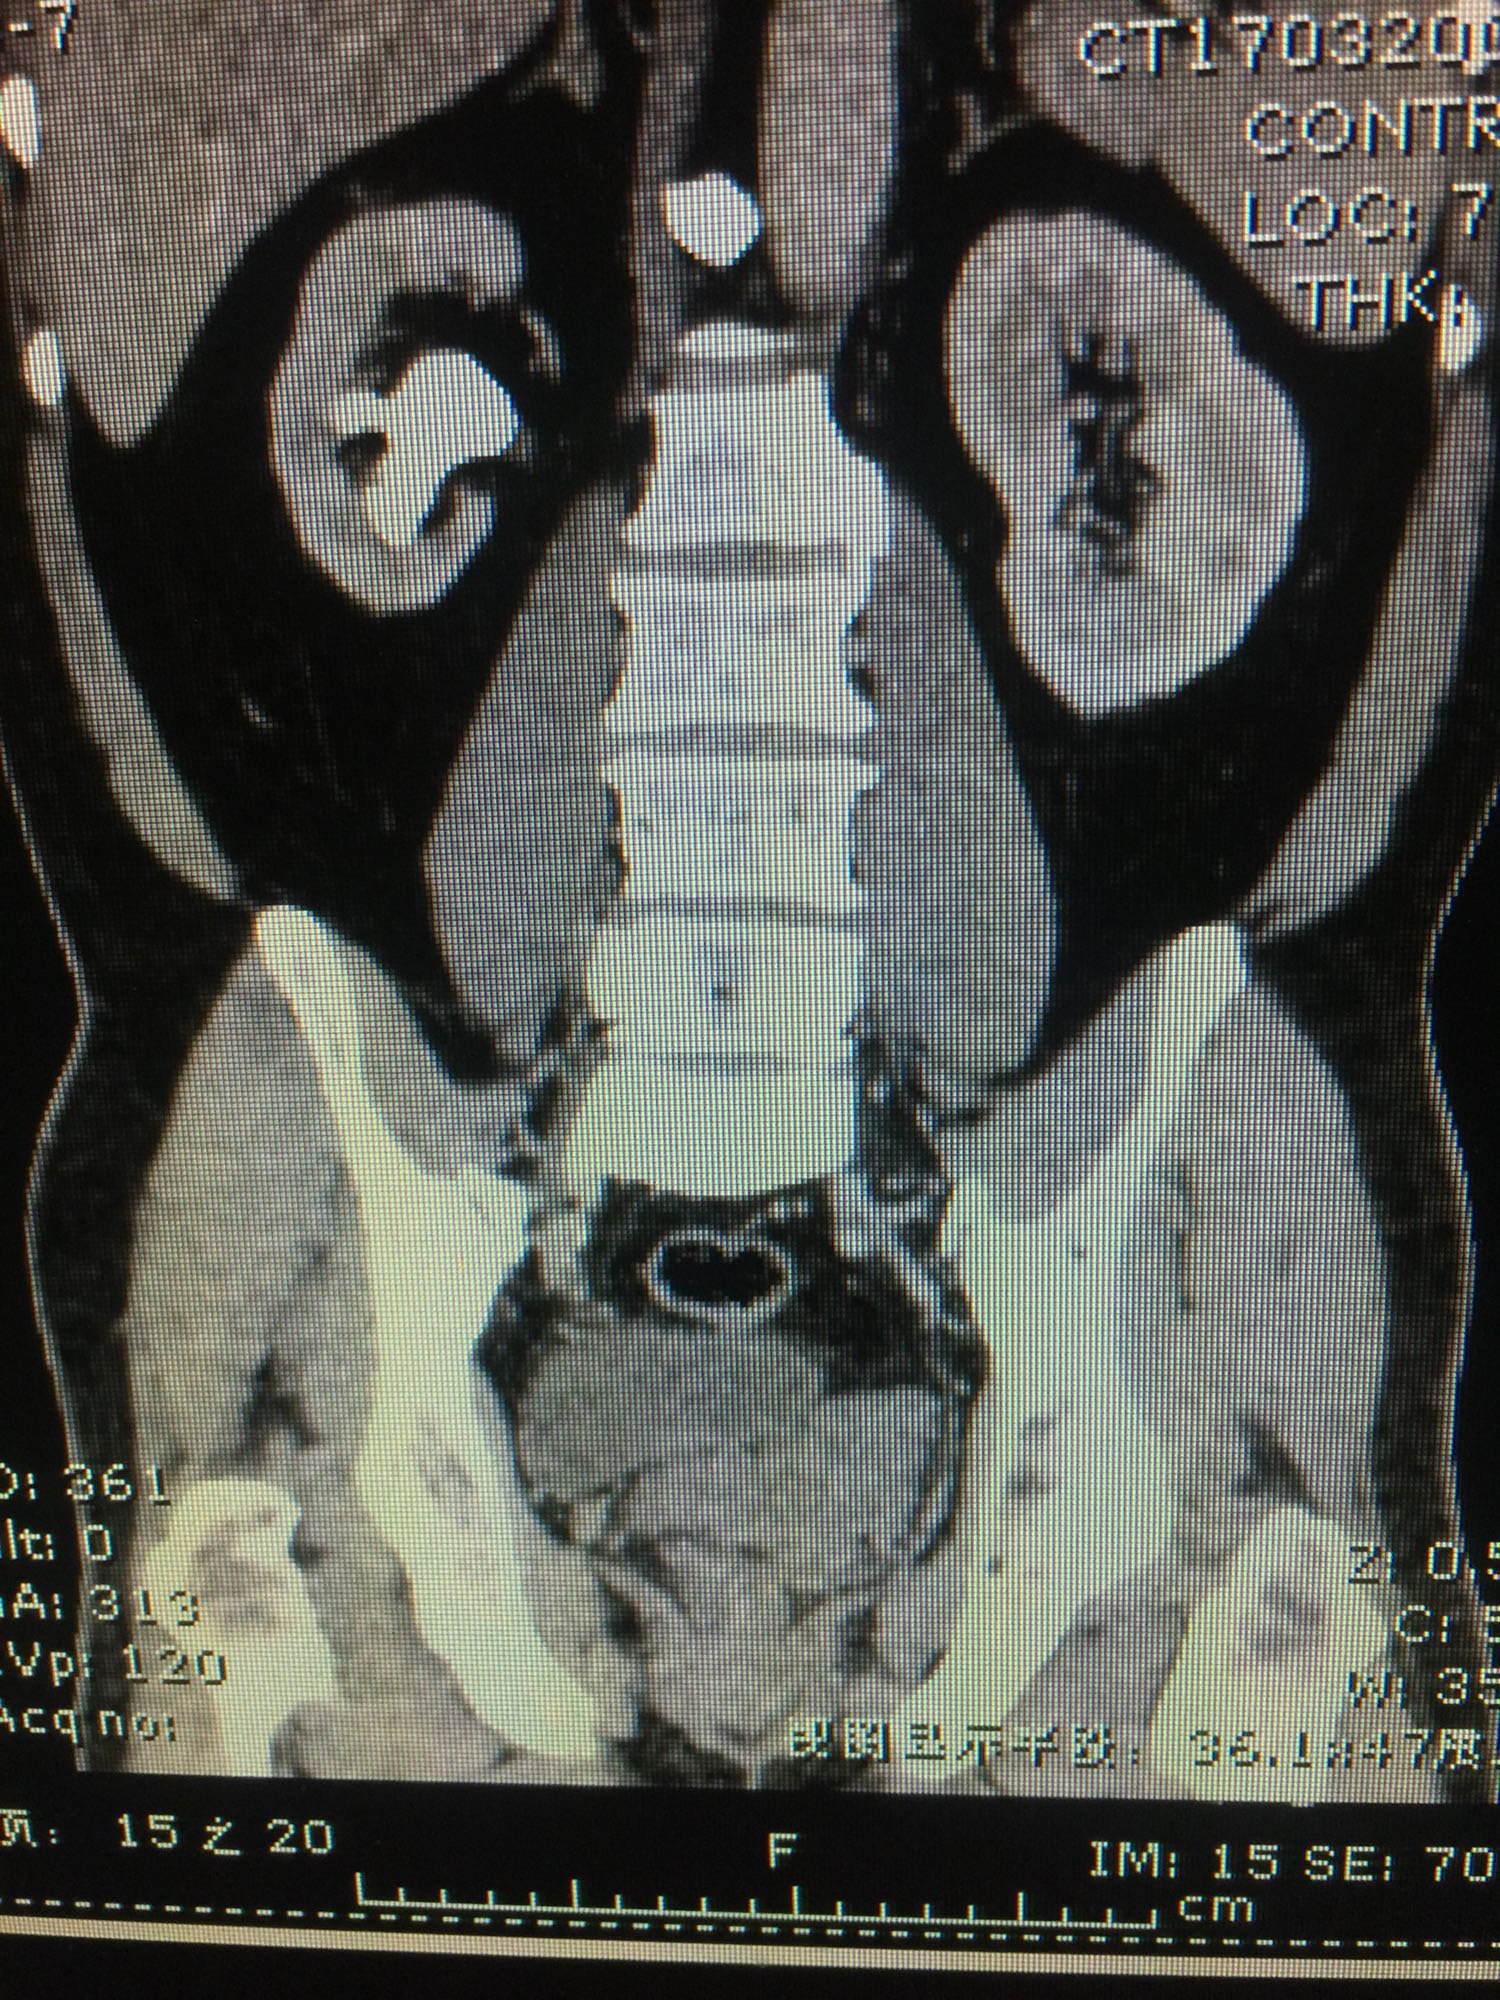

查体:双肾区无叩压痛,膀胱区无叩压痛,无叩浊,前列腺二度,质地中等,无压痛,无结节。CTU提示右肾铸型结石。ECTL 40,R14.5

右肾铸型结石 予以经皮肾碎石治疗,术后复查平片未见结石残留。